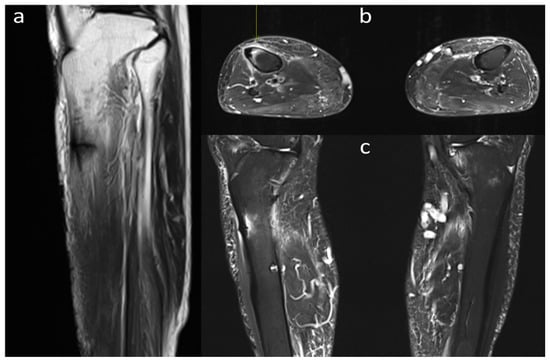

2. Case Presentation